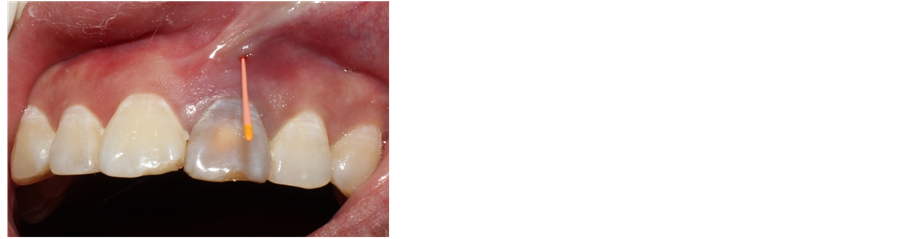

A 28-year-old female patient was treated in Department of Stomatology, Fujian Medical University Union Hospital on March 11th 2016 with chief complaint of “gingiva of the left upper anterior tooth suppurated for one month”. A decade ago, the patient had tooth trauma. One year ago, the patient had root canal therapy in other hospital for the 21st tooth. One month ago, the patient was treated in our hospital for repeated suppuration at gingiva of the 21st tooth. The patient is healthy in the past, denying systematic disease, infectious disease, drug allergy history, poisoning history and trauma history in last ten years. Clinical para-oral examination (Figures 1-2): The maxillofacial region is basically symmetrical in left and right; no tenderness in temporal-mandibular joint and no click and fricative when opening and closing mouth; parotid gland is normal in palpation; no swelling in lymph gland. Intraoral examination: there is tooth stain and fistula at gingiva in the 21st tooth, the crown is dark and 21 (++) is not loose, the teeth of the teeth were normal and the 11 teeth were cut by 1/3. X-ray periapical film shows (Figure 3): 21st tooth is low-density shadow under large-area and high-density projection at apex with defective root filling. The patient wanted to improve the tooth color without wearing too much tooth when solving the suppuration at apex.

Figure 2. Gingival fistula.